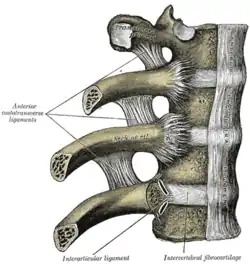

Vertebral arches of three thoracic vertebrae

Vertebral arches of three thoracic vertebrae Costovertebral joints seen from the front